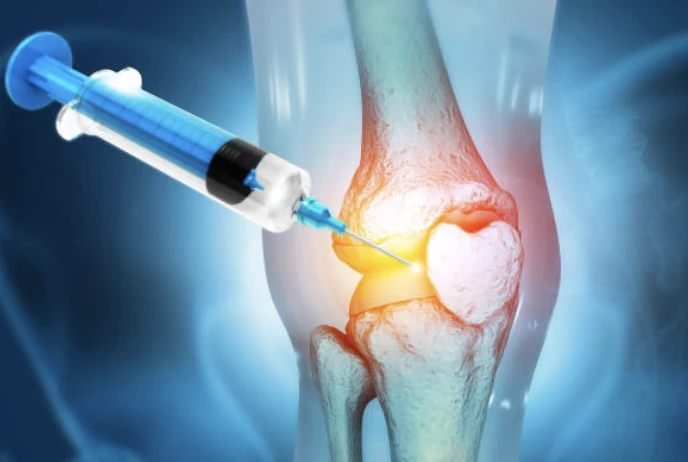

- 증식치료 : 비수술치료로 약해진 인대를 튼튼하게 강화시켜 주는 간편 주사 시술입니다.